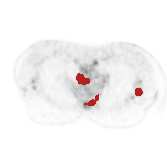

There has been growing research interest in using deep learning based method to achieve fully automated segmentation of lesion in Positron emission tomography computed tomography(PET CT) scans for the prognosis of various cancers. Recent advances in the medical image segmentation shows the nnUNET is feasible for diverse tasks. However, lesion segmentation in the PET images is not straightforward, because lesion and physiological uptake has similar distribution patterns. The Distinction of them requires extra structural information in the CT images. The present paper introduces a nnUNet based method for the lesion segmentation task. The proposed model is designed on the basis of the joint 2D and 3D nnUNET architecture to predict lesions across the whole body. It allows for automated segmentation of potential lesions. We evaluate the proposed method in the context of AutoPet Challenge, which measures the lesion segmentation performance in the metrics of dice score, false-positive volume and false-negative volume.